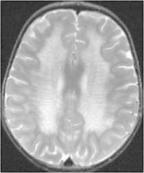

異染性腦白質營養不良

• 異染性腦白質營養不良

628健康網為您分享有關異染性腦白質營養不良的癥狀,異染性腦白質營養不良的治療方法,異染性腦白質營養不良的預防知識...